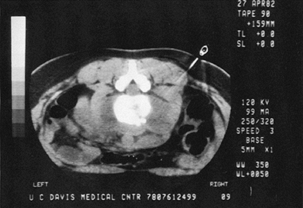

The definitive procedure for accurate diagnosis of postoperative

discitis is CT-guide neddle biopsy followed by culture of the organism

from the disc space (Fig. 150.14).

Figure 150.14. CT shows a needle being directed into a paravertebral abscess surrounding an infected vertebra.

|